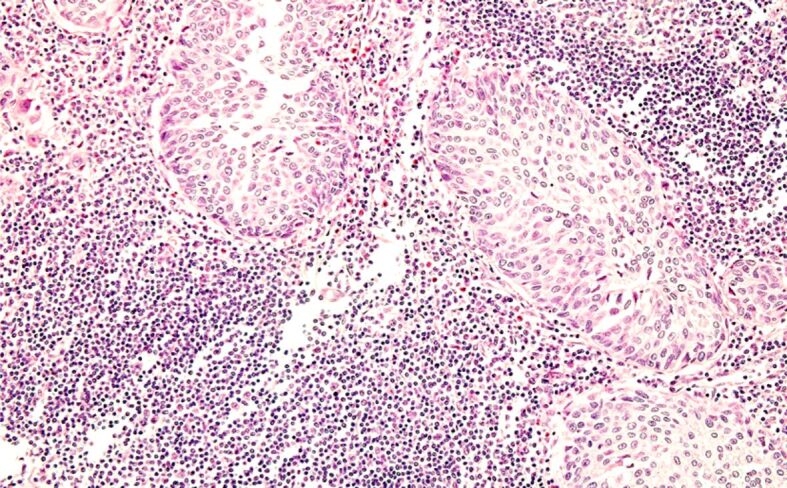

Incidental prostate carcinoma (iPC) is a subject of debate concerning its definition, incidence, biology, diagnosis, staging, and treatment. The present study aimed to assess the incidence and main clinical-morphological characteristics of iPC identified in radical cystoprostatectomy (RCP) specimens over a 5-year period. Using the database of the Urology and Pathology Departments, we identified all patients with bladder carcinomas (BCs) who underwent RCP within a 5-year frame time. We selected only those patients with synchronous BC and prostate carcinoma (PC). The following parameters were analyzed for these patients: age, type of bladder and prostate tumor, degree of differentiation, pathological stage, and other prognostic parameters. We identified 91 men with bladder tumors treated by RCP among whom 43, aged between 53 and 84 years (mean age: 69.2 years), presented synchronous PC. iPC was more prevalent in older individuals (>65 years: 30 patients, 69.8%), with only six out of the 43 (12.8%) patients with iPC being aged ≤60 years. All iPC cases were conventional adenocarcinoma. Well-differentiated prostate adenocarcinomas (grade group 1) predominated (65.1%). Among the 43 iPCs, 16 (37.2%) were clinically significant PCs. iPC is frequently identified in patients with BC when inclusion and evaluation of all or most of the prostate tissue are performed. Although more than half of iPCs were well-differentiated tumors confined to the prostate, a significant number of cases met the criteria of clinically significant PC. All men over the age of 50 who are candidates for RCP, should undergo evaluation through serum prostate specific antigen determination.

Abstract Image